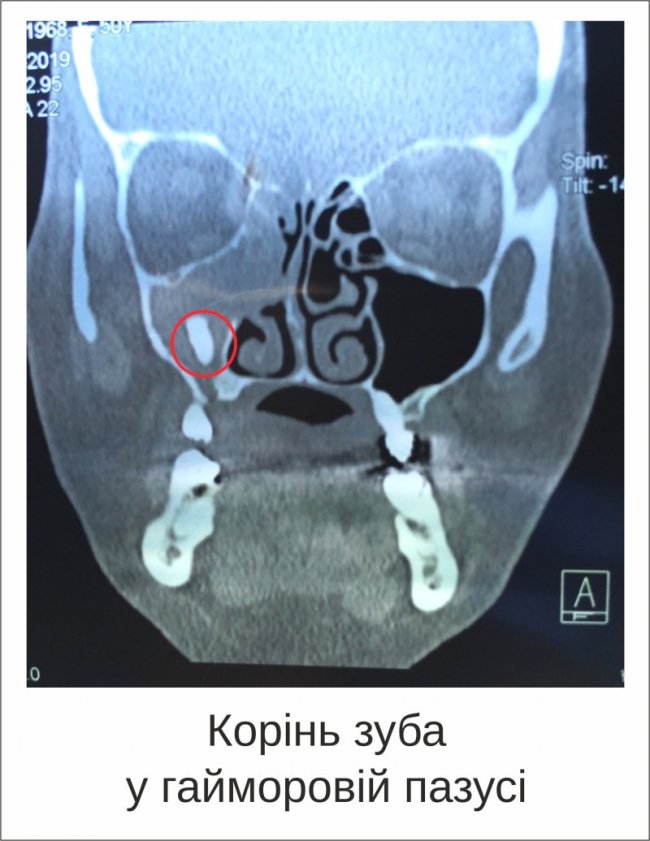

У Луцькій міській клінічній лікарні у 54-річної пацієнтки видалили шматок кореня зуба, який потрапив у гайморову пазуху.

У лікарні пацієнтці зробили комп’ютерну томографію. З’ясувалось, що у її правій гайморовій пазусі одразу дві проблеми – корінь зуба і грибкове утворення міцетома.

«Близько двох років тому з цього боку жінці видаляли зуб. Частина кореня зуба залишилася, проламала стінку гайморової пазухи і потрапила всередину неї», - пояснив лікар-отоларинголог.